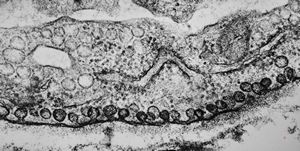

M,59y. | endothelial Weibel-Palade tubular body - angiomatous tumor, v.s.Kaposi